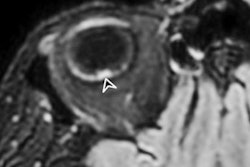

Although the disease tends to be less severe in children, these patients can develop more severe, hyperinflammatory forms of the illness such as single or multiorgan dysfunction, Kawasaki-like disease, myocarditis, and serositis. Echocardiography, ultrasound, and chest CT illuminate the disease's progression, Tomà concluded.